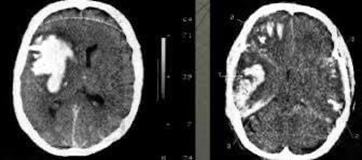

нтузионные очаги на кт

Контузионные очаги на кт 27 фото